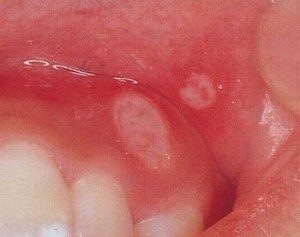

- アフタ性口内炎

ストレスや睡眠不足

そもそも口内炎とは、口の中や周辺の粘膜炎症で、何らかの原因により粘膜に刺激が生じ、上皮に炎症が起こり、ただれた状態のことです。